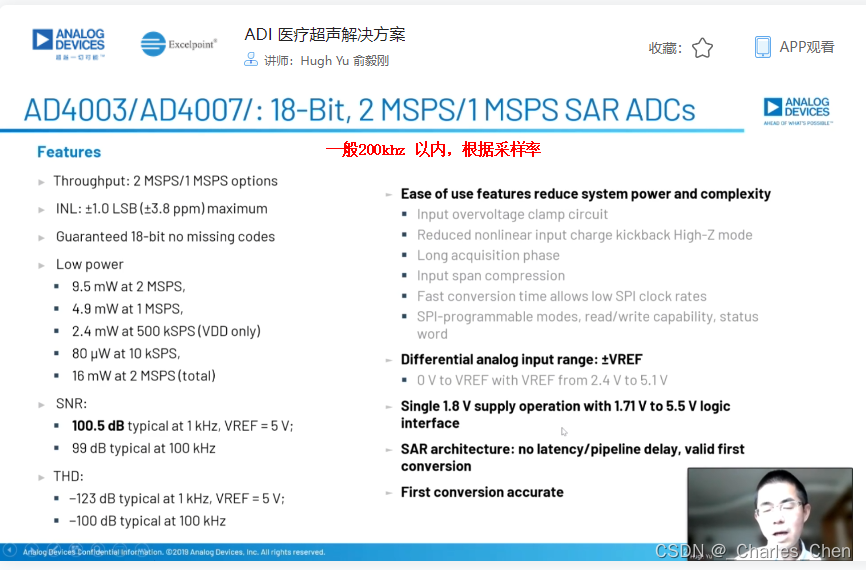

抗混叠滤波器(AAF)和ADC

抗混叠滤波器AAF置于接收通道,用于滤除高频噪声和超出正常最大成像频率范围的信号,防止这些信号通过ADC转换混叠至基带。设计中大多采用可调节的AAF,为了抑制混叠并保证信号的时域响应,滤波器需要对第一奈奎斯特频率以外的信号进行衰减。因此,常常使用巴特沃斯滤波器或更高阶的贝塞尔滤波器。

典型应用中采用12位ADC,采样率通常在40Msps至60Msps之间。ADC提供必要的瞬态动态响应范围,同时具有适当的成本和功耗。在设计得当的接收器中,ADC会限制接收通道的瞬态SNR。如上所述,性能差的VGA会限制整个接收通道的SNR指标。